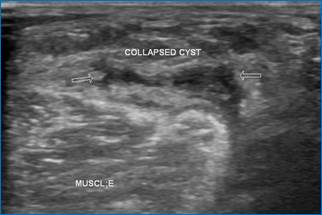

Спавшаяся киста и киста небольшого размера может не вызывать беспокойства у пациента (рис.4).

Рис. 4. Киста Бейкера («спавшаяся»)